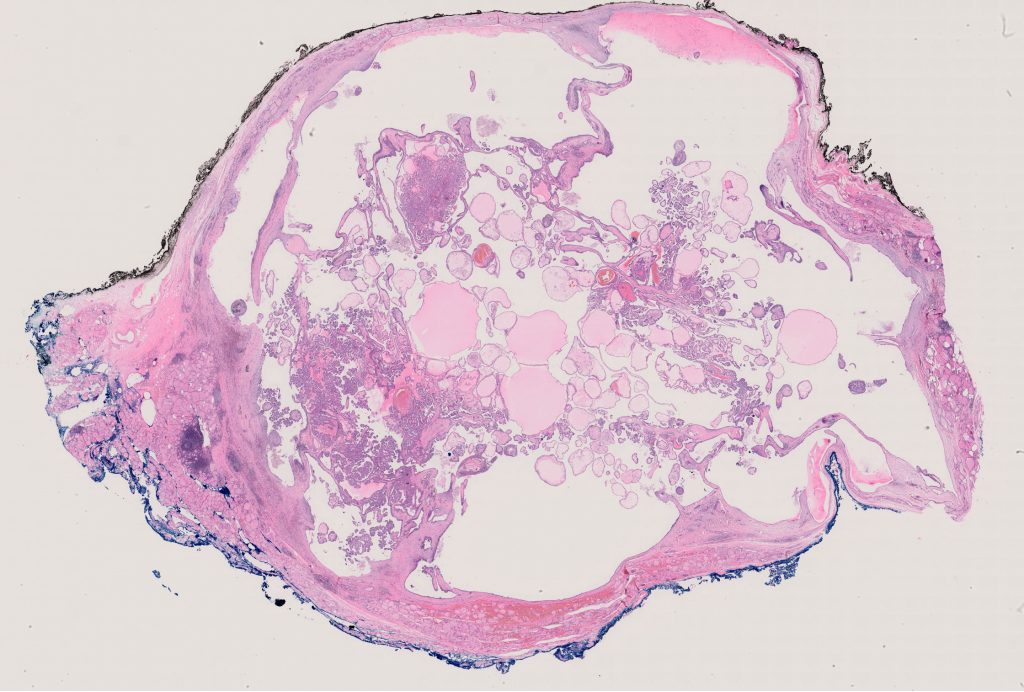

Nikiforov Singapore Study\TSN519

TSN 519.ndpi

143360

x

96768

40X